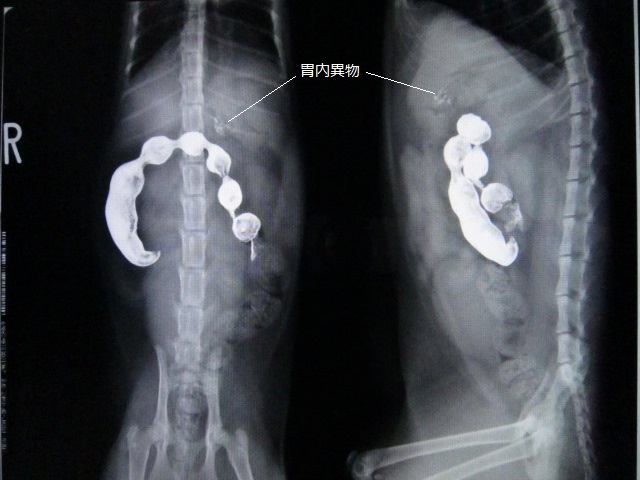

バリウム投与2時間後のレントゲンです。

ちょっと見えにくいですが、胃内に異物があります。